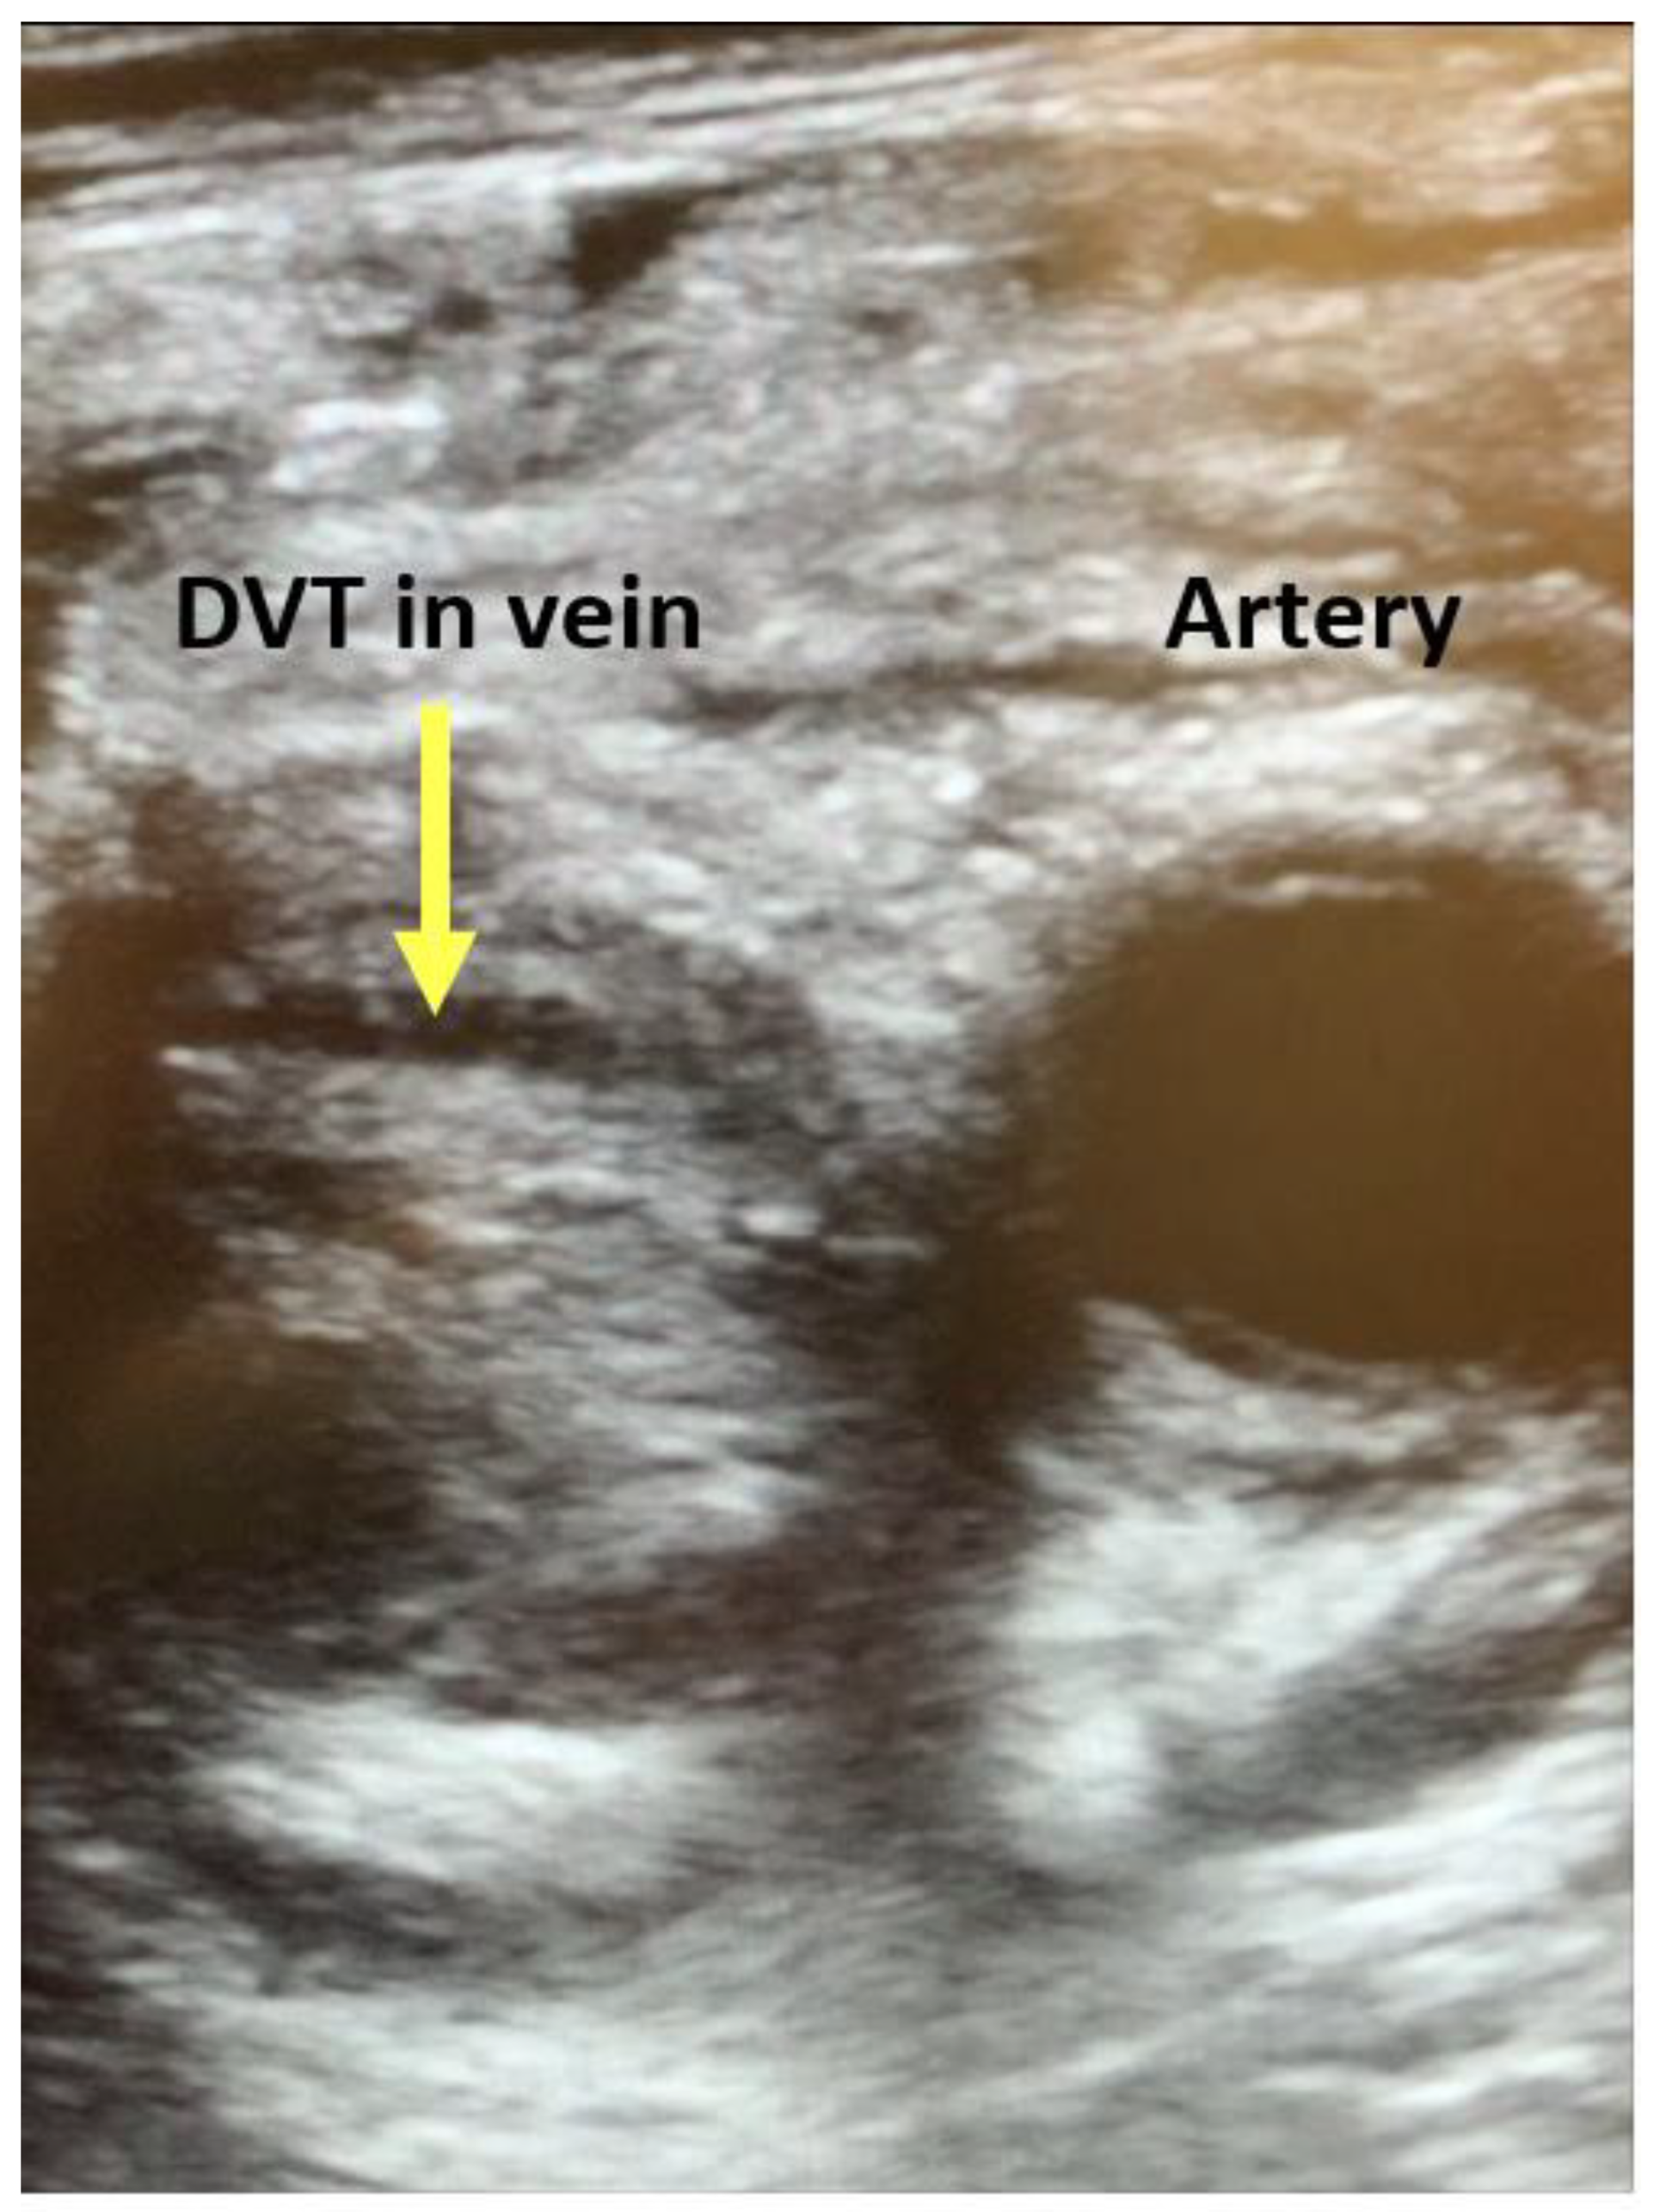

| Assessment of peripheral vasculature for size, disease, thrombus | Assessment for vascular or intracardiac injury (dissection, tamponade) | Assessment of aortic mixing point |

| Assessment of peripheral vasculature for size, disease, thrombus | Assessment of return (outflow) “jet” | Confirmation of cannula position |